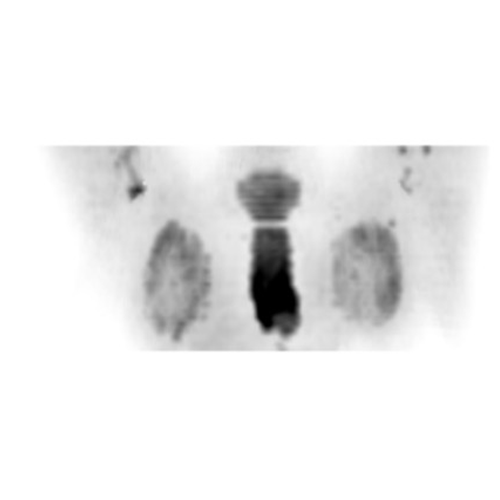

全身DWI

腹部

乳房DWI